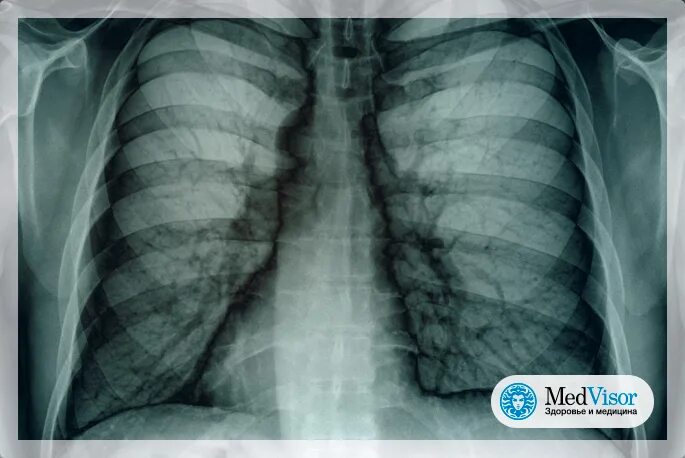

Снимок курящих легких